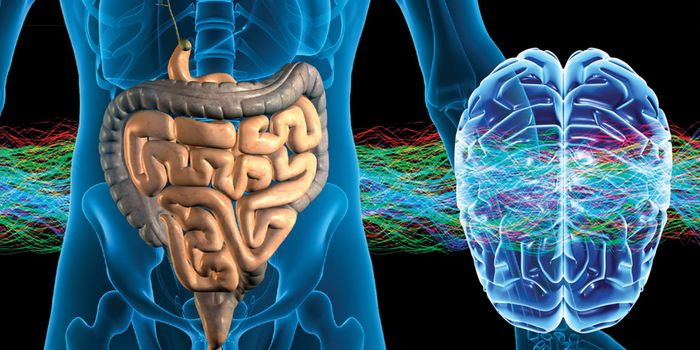

DEC 20, 2019NeuroscienceResearch is increasingly pointing towards the importance of the gut-brain axis in regulating our health. Not only has th ...

AUG 22, 2017MicrobiologyYour gut is a long way from your brain, but problems with your gut microbiome could lead to problems with your brain by ...

JUN 30, 2022NeuroscienceThere is an ever-increasing number of links that are being found between microbes in the human gut and our health. Resea ...